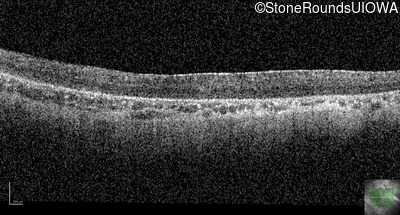

Optical Coherence Tomography - Right - 10/300 sc

Exemplar / OCT Stack

OCT Stack